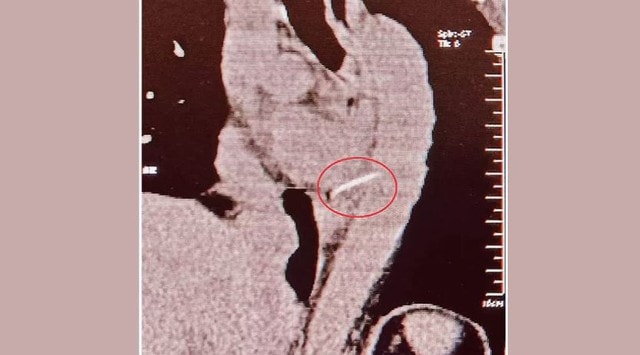

Sau đó, bà bị đau ngực dữ dội và được đưa đến Bệnh viện Apollo, nơi chụp CT cho thấy xương đã đâm vào động mạch chủ, động mạch chính gần tim bằng cách đâm xuyên qua thực quản.